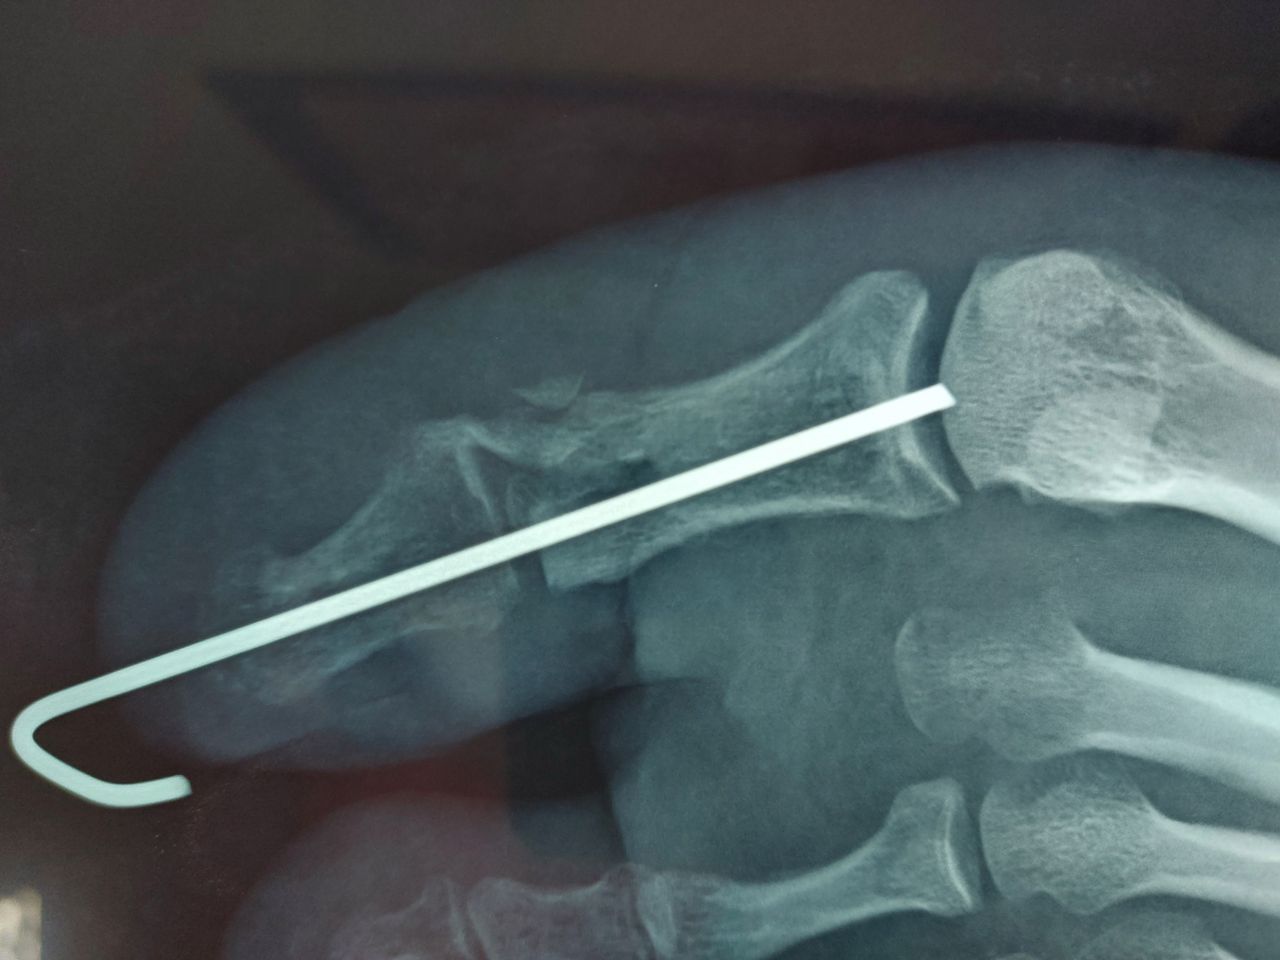

Mi sono formato negli anni, conseguendo diplomi , attestati, lauree ed ancora corsi di aggiornamento . Credo di conoscere sufficientemente la medicina per quello che attiene il mio campo di interesse e azione. ho scritto alcuni articoli mai pubblicati. ho un mio metodo, oramai consolidato, di approccio del paziente basato sull'accoglienza, gentilezza ma anche erudizione e spiegazione del motivo di consultazione . Mi piace mettere a proprio agio il/la paziente. Le mie tecniche spaziano da quelle viscerali , strutturali, cranio sacrali nell'ambito osteopatico e riabilitative e neuro-riabilitative nel campo del disequilibrio , vestibolare e patologico degenerativo. Mi occupo di traumatologia post chirurgica e protesica inoltre di riabilitazione mio-funzionale della lingua e temporo-mandibolare in ambito odontoiatrico.